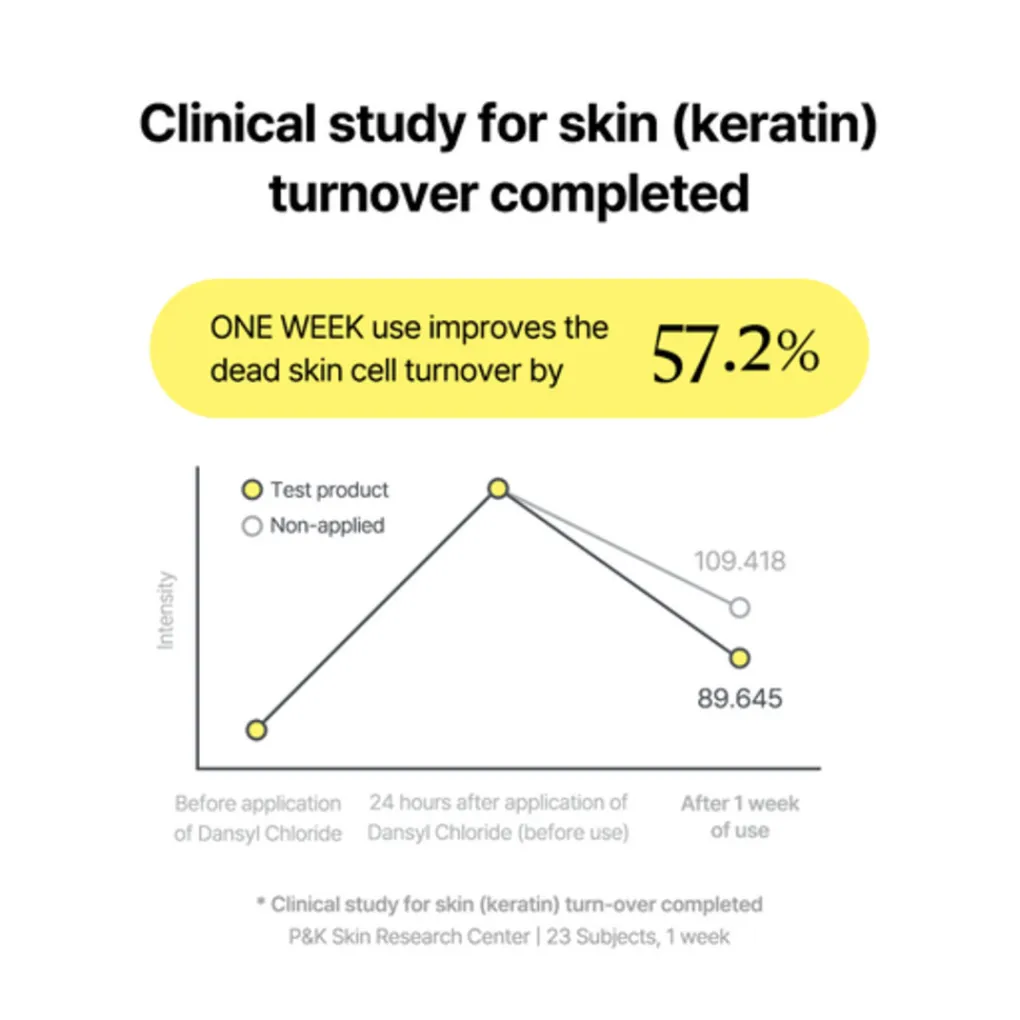

De By Wishtrend Propolis Energy Boosting Essence is een voedende en verzachtende essence die de huid een gezonde, natuurlijke gloed geeft. Verrijkt met propolisextract, honing en andere hydraterende ingrediënten helpt deze essence de huidbarrière te versterken, irritaties te kalmeren en de huidtextuur zichtbaar te verbeteren. Ideaal voor de doffe of gevoelige huid die behoefte heeft aan extra energie, hydratatie en bescherming tegen externe invloeden.